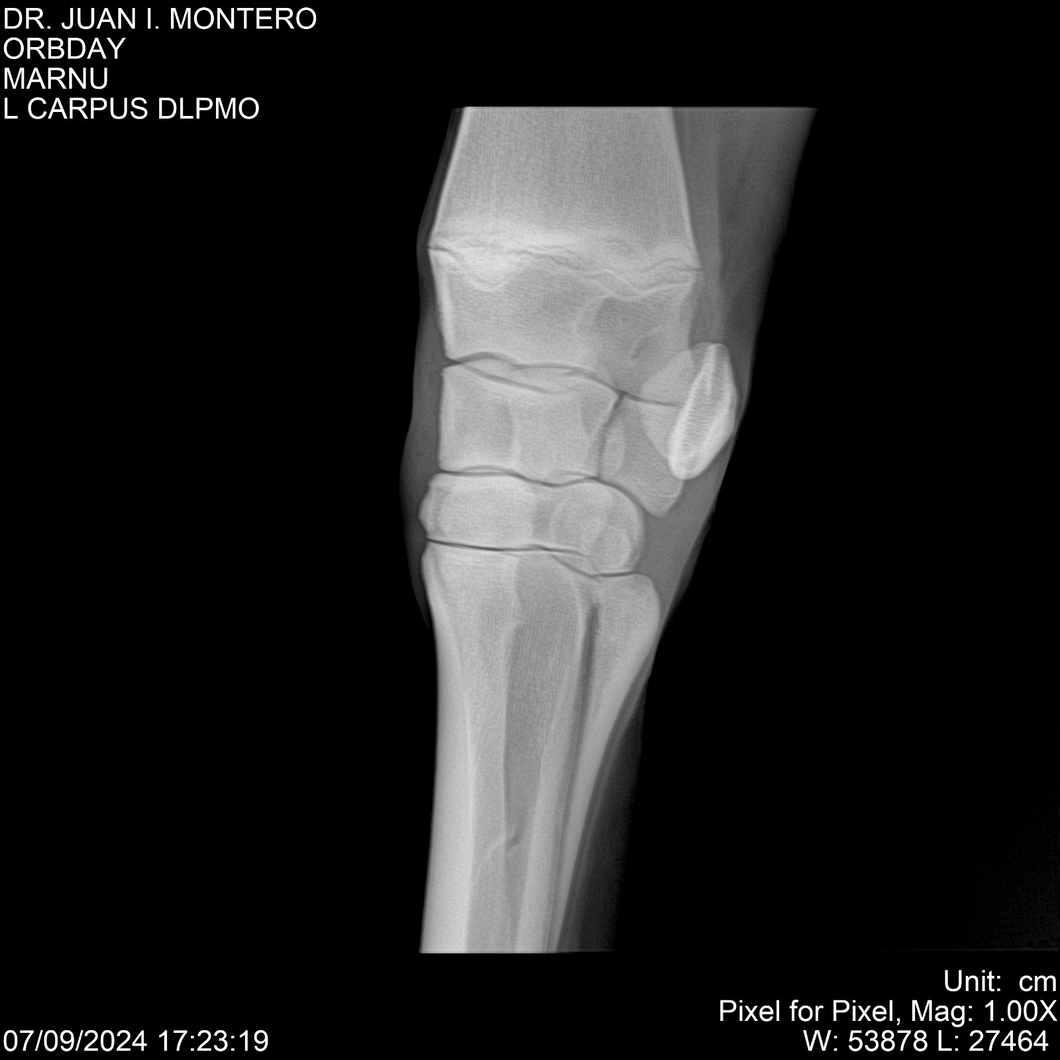

Visualizaciones